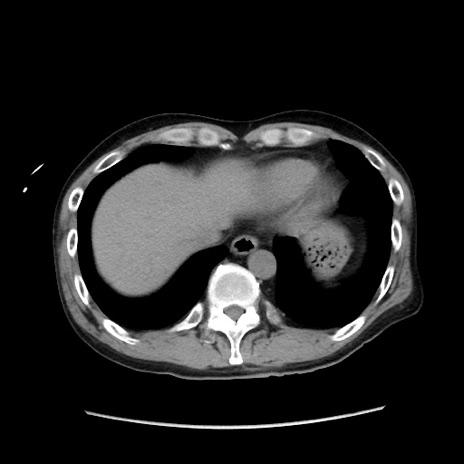

冠状断像

【症例】40歳代 男性

【主訴】腹痛

【現病歴】4時間ほど前に電車に乗車中に臍部上より腹痛出現。徐々に増悪し起立困難となり、救急外来受診。生ものは数日食べていない。今朝お雑煮を食べた。

【身体所見】BT 36.8℃、BP 117/84mmHg、HR 91/min、SpO2 97%、苦悶様、腹部:臍上部広範囲圧痛あり、反跳痛±

【データ】WBC 8100、CRP 0.03